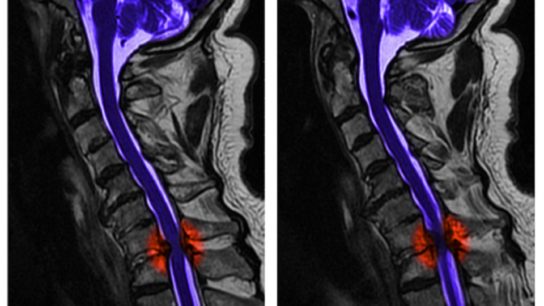

In a randomized clinical trial, researchers determined whether early surgical treatment yields better motor recovery than delayed surgical treatment for patients with cervical spinal cord injury.